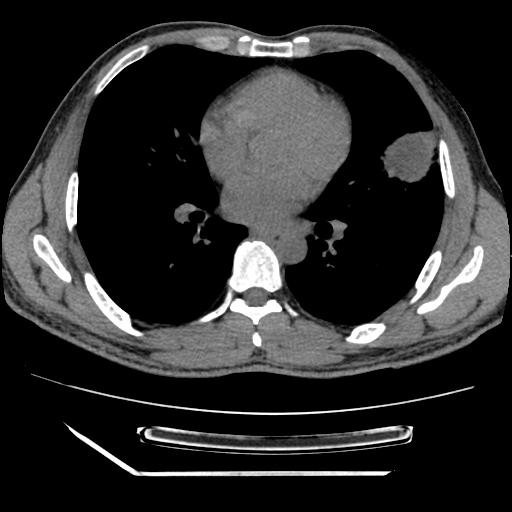

男,38岁,于2009年8月9日晚突发左侧胸痛,今x线提示左下肺阴影,为了明显确诊断,行ct检查,

血常规:嗜酸性细胞增高,单核细胞增高。

纵膈窗

病灶发生在下叶,密度均匀,边缘模糊、毛糙,周围血管纹理增强扭曲改变,靠近胸膜处病灶胸膜反应明显。

支持考虑---球形肺炎。

左肺舌叶病变。主体病灶呈类圆形中心密度低,成液化趋势周边班片影分布

考虑肺脓肿

虽然实验室检查支持炎性病变,且病变内有坏死改变(中央呈大片状低密度影),但仍不能掉以轻心,鳞癌也可以有这种影像改变。